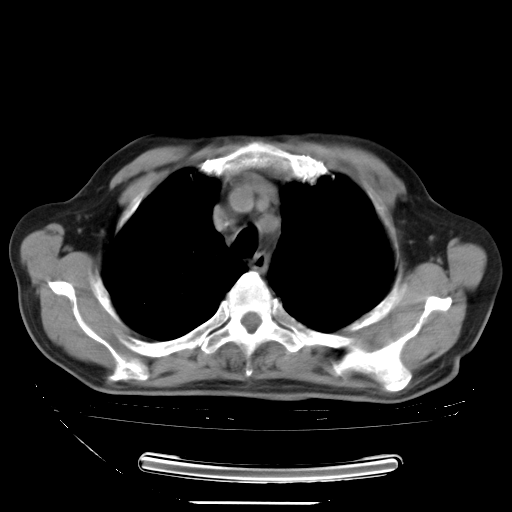

今天复查肺部CT,发现双肺广泛磨玻璃样改变。所以我把3月19日和5月9日相隔50天的肺部CT上传。请大家会诊。

2009年3月19日肺部CT片。

2009年3月19日肺部CT